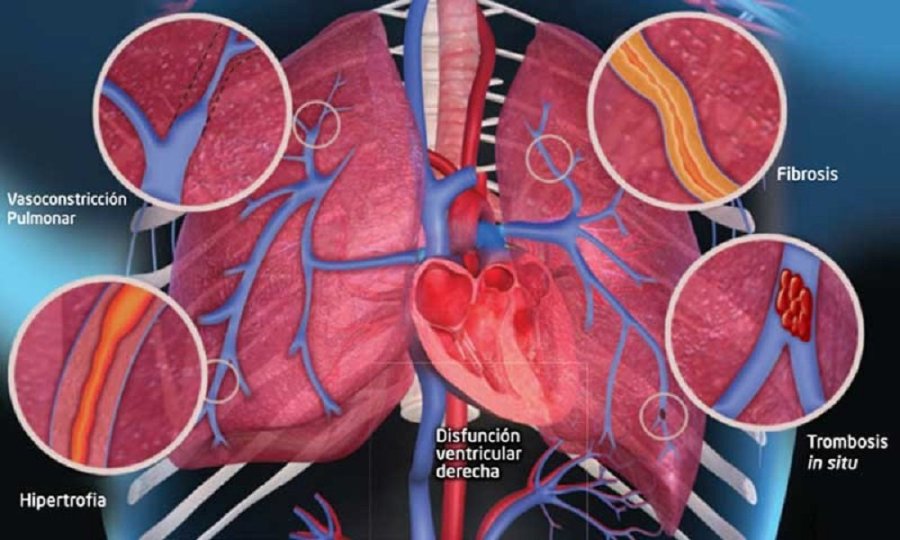

La hipertensión arterial pulmonar hace que el corazón trabaje más de lo normal para bombear sangre a los pulmones. El lado derecho del corazón bombea sangre a través de las arterias pulmonares a los pulmones para recoger el oxígeno y luego retornar al lado izquierdo para distribuir sangre oxigenada hacia el resto del cuerpo. Cuando las pequeñas arterias de los pulmones se estrechan, no pueden transportar la cantidad suficiente de sangre y la presión aumenta. El esfuerzo del corazón en contra de dicha presión conduce a que el lado derecho del corazón se vuelva más grande y comience a fallar, lo que conduce a la insuficiencia cardíaca.

La principal complicación crónica de la hipertensión arterial pulmonar es la insuficiencia cardíaca4. Las enfermedades cardiovasculares aún presentan ciertas carencias en términos de tratamientos y esto impulsa la búsqueda de medicamentos transformadores que tengan el potencial de redefinir el panorama del tratamiento y mejorar la atención al paciente3.